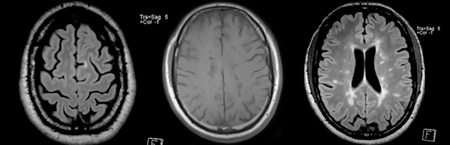

• Ressonância magnética

Ressonância magnética

• "aumento do número de lesões supratentoriais (…) no estudo medular não se destacam seguras lesões de novo"